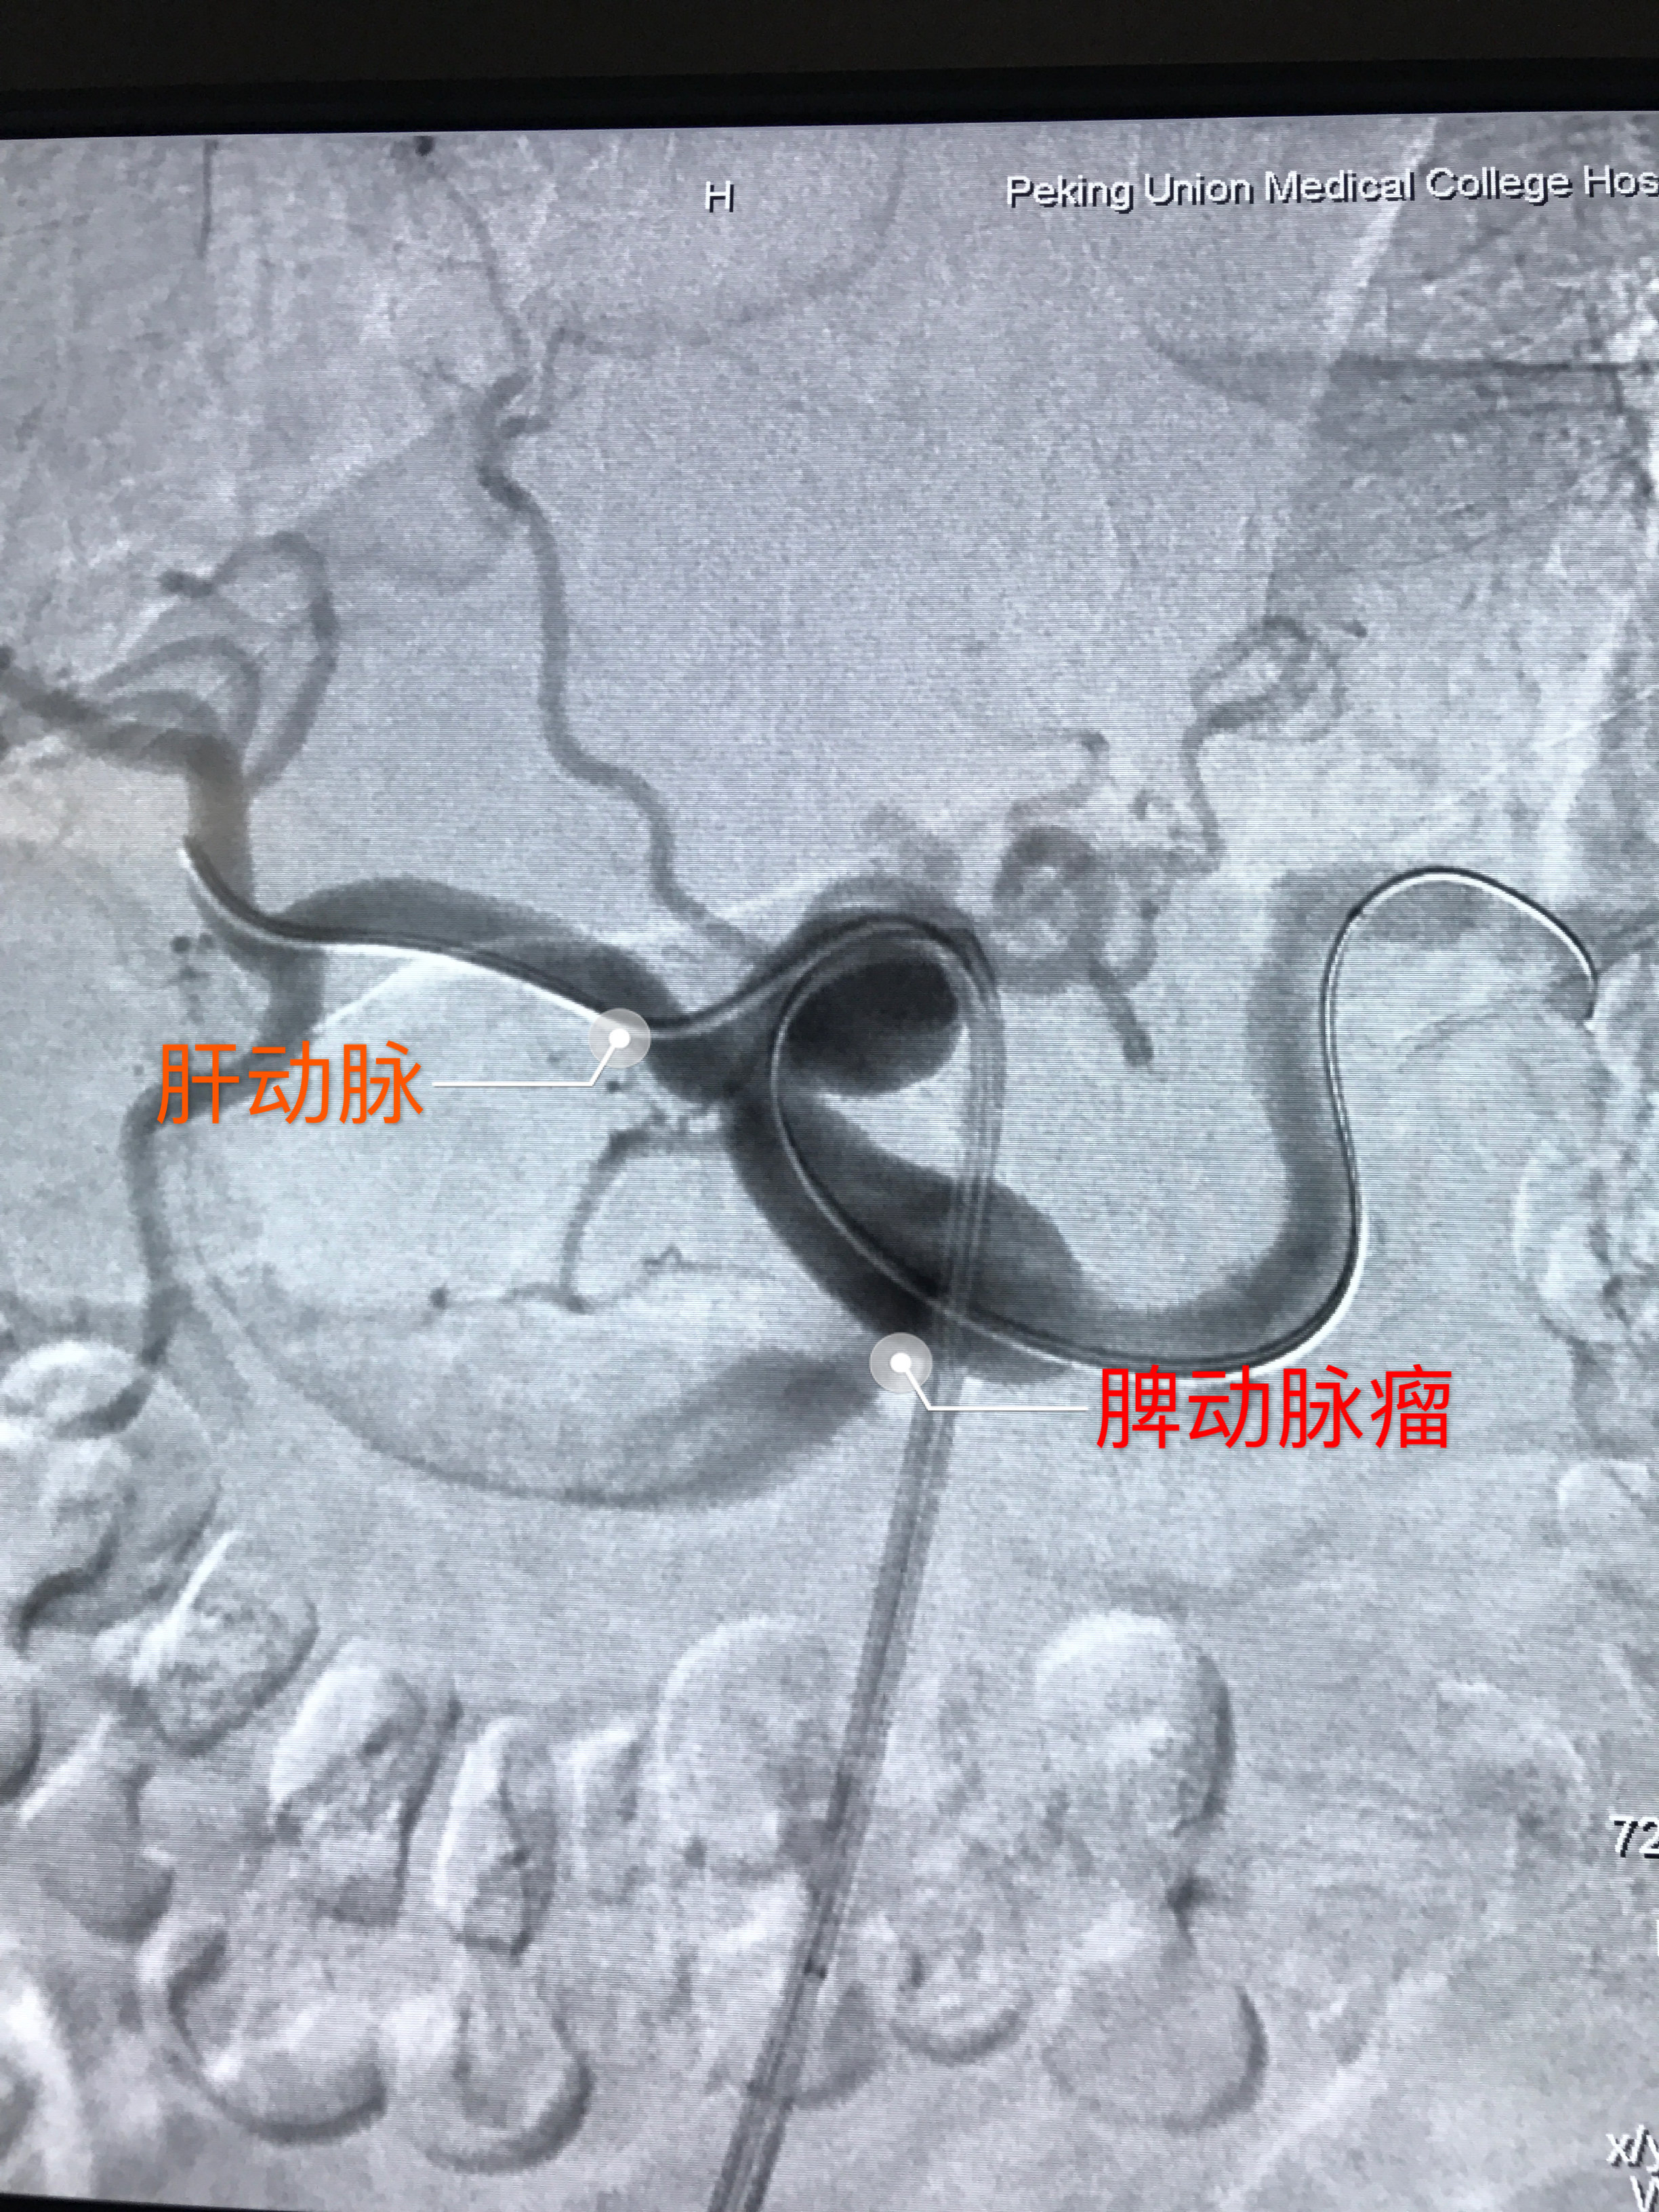

脾动脉瘤介入栓塞病例(邯郸市第一医院介入外科 夏化文主任介入团队)

微创治疗腹腔干夹层和脾动脉瘤

论著|脾动脉瘤12例治疗方式选择及疗效分析